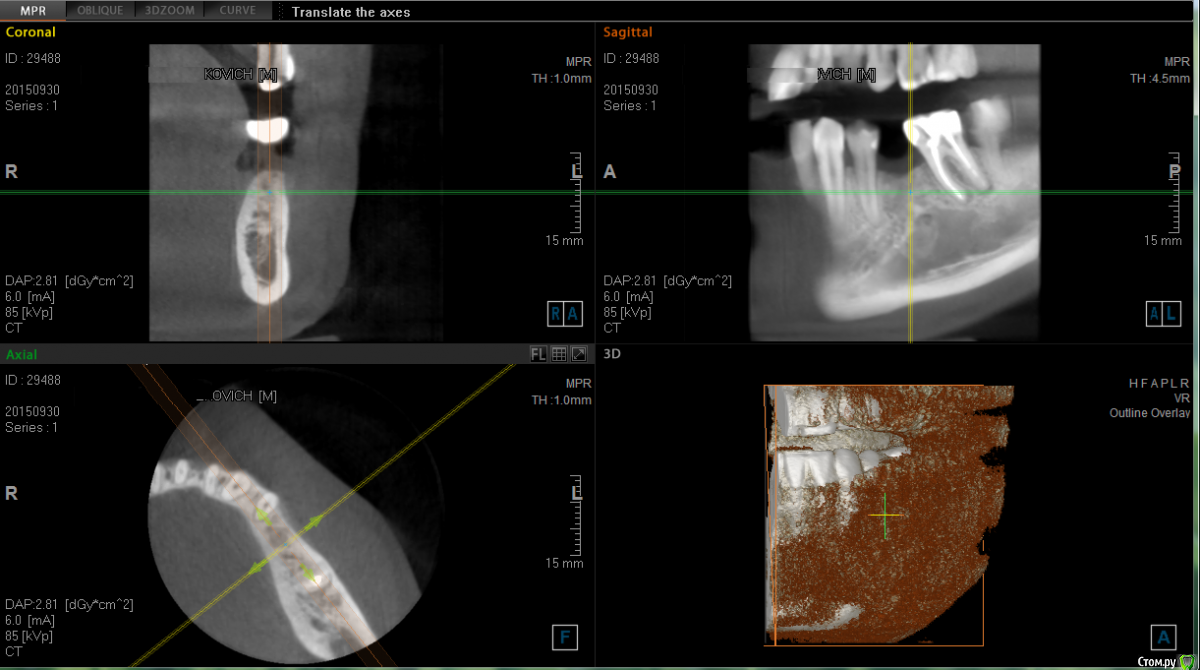

hisurfer Опубликовано 7 октября, 2015 Поделиться Опубликовано 7 октября, 2015 Добрый день!В конец марта этого года мне установили имплант roott , через месяц начался переимплантит, пришлось удалить.На вопрос, почему произошло отторжение, врач ничего толком не ответил, кроме возможной аллергии на титан (или сплав импланта), предложил попробовать установить еще раз через 2 месяца, когда кость заживет.Я решил второй раз не пробовать на авось, притом что причина первой неудачи осталась неясна. Сейчас интересует вопрос, возможно ли по снимкам определить, почему произошло отторжение?Также нужен совет по дальнейшему лечению. Хочу еще раз попробовать установить имплант.Уже консультировался, но хотелось бы услышать еще мнения, ибо страшно. Приложил снимок сразу после установки импланта (1) и перед удалением (2), и скрины кт недельной давности.При необходимости могу выложить полный КТ. Благодарю! 2_20150423 14-28-17.bmp Ссылка на комментарий

Bier Опубликовано 21 октября, 2015 Поделиться Опубликовано 21 октября, 2015 не рекомендую ставить имплантаты ROOTT и прочие из этой линейки. Скорее всего это слишком агрессивный имплантат для плотной кости (в вашем случае) 2 Ссылка на комментарий